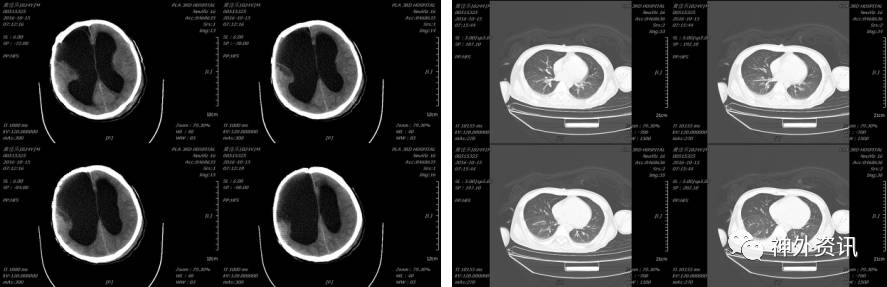

第四日复查胸部及脑CT示(2016-09-16 15:29):

2016-09-30患者再次出现出现咳嗽,发热38.6度,血常规:白细胞(WBC)21.78×109/L,中性细胞比率(NE%)88.4%,继续给予舒普深等药物, 2016-10-04血常规:白细胞(WBC)8.40×109/L、中性细胞比率(NE%)66.5%,复查胸部CT示:

2016-10-15复查头颅CT示:拔出引流管后未见脑室继续扩大。

胸部情况较前明显好转,于2016-12-01再次复查头颅CT示未见脑室进一步扩大。

2017-03-30头颅CT示: